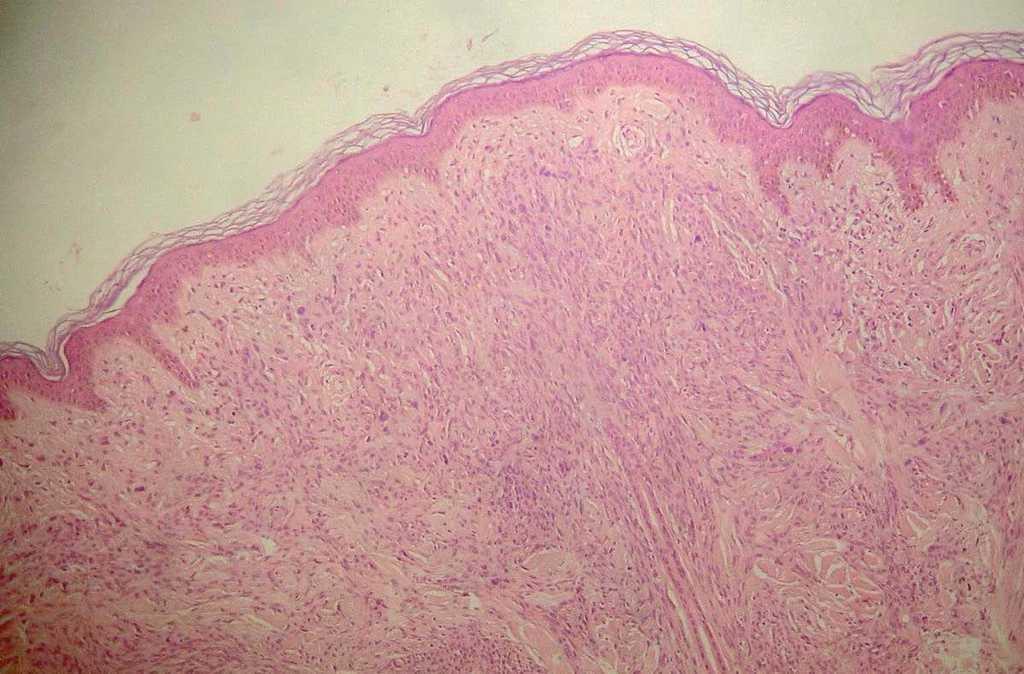

Se realizó la extirpación completa de la lesión y se procedió a su posterior estudio histológico, en el que se apreciaba una lesión compuesta de células melanocíticas pleomorfas en dermis que profundizaba hasta tejido celular subcutáneo con un borde romo bien definido (fig. 2). La lesión estaba constituida por células epitelioides y fusiformes que disecaban las fibras de tejido conjuntivo, rodeaban los tallos pilosos e infiltraban las glándulas ecrinas y el tejido graso (fig. 3). No se identificaron atipias ni mitosis. Con técnicas de inmunohistoquímica las células eran S 100 y Melan A positivas y HMB 45 negativas.

Figura 2.